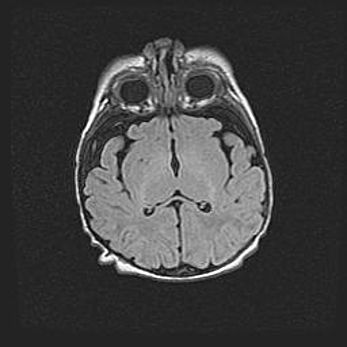

Сообщающаяся гидроцефалия. Кистозная энцефаломаляция головного мозга.

Возраст: 3 месяца 4 дня

Вес: 3100 г

Пол: женский

Окружность головы: 34 см

Срок гестации: 31 неделя

Кистозная энцефаломаляция головного мозга - одна из форм поражения головного мозга в детском возрасте. Характеризуется возникновением множественных и распространённых кист в коре, белом веществе и подкорковых образованиях головного мозга у плодов, новорождённых и детей раннего возраста. Развитие кистозной энцефаломаляции связано с внутриутробной асфиксией и гипотонией, родовой травмой, тромбозом синусов, пороками развития сосудов, инфекциями, сепсисом и другими причинами. Наиболее значимые инфекционные агенты: вирусы простого герпеса, цитомегалии, краснухи, токсоплазмы, энтеробактерии, золотистый стафилококк и другие.